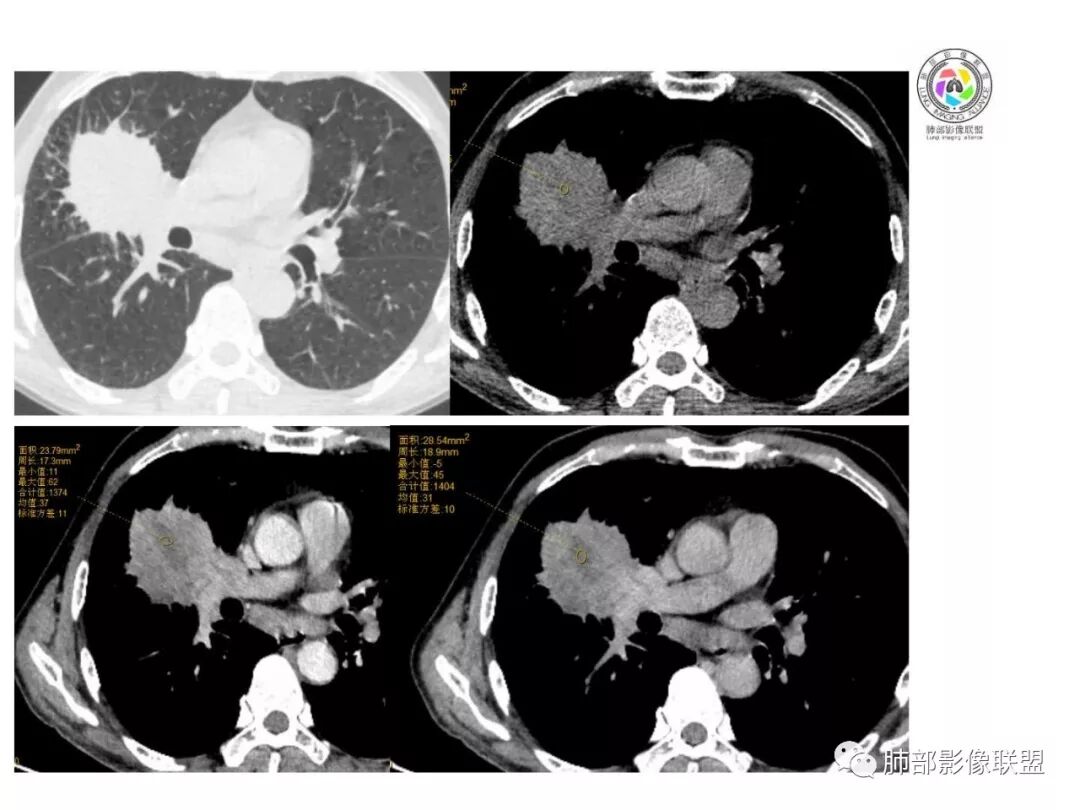

患者中老年男性,体检发现肺部占位。

胸CT:右肺中叶实性占位性病变,呈膨胀性生长,对斜裂明显挤压,右肺中叶外侧段阻塞,并在边缘可见分叶、毛刺、棘突样改变,胸膜牵拉;增强可见病灶明显强化,可见边缘模糊血管影,病灶内可见大片状低密度区,隆突下可见肿大淋巴结。

诊断考虑:恶性病变。

患者中老年男性,体检发现右肺占位。血常规轻度贫血,AFP、CEA正常,肝肾功能、血糖、血脂、心肌酶、电解质正常。胸部CT:右肺中叶巨大肿块灶,垮叶生长,可见分叶、毛刺、血管集束、支气管截断征象,远端周围可见小叶间隔增厚,增强轻度强化,内可见低密度坏死区,综合淋巴结肿大,且可见淋巴结内似低密度灶。综合考虑恶性,鳞癌并癌性淋巴管炎可能大。鉴别结核、腺癌。

胸CT:右肺中叶团块样实性占位,边缘膨隆,中叶外侧段阻塞,病灶可见深分叶、棘突,胸膜牵拉;增强不均匀强化,可见边缘模糊血管影,病灶内大片状低密度区,纵隔多发肿大淋巴结。

诊断考虑:恶性病变,鳞?大细胞?鉴别:TB